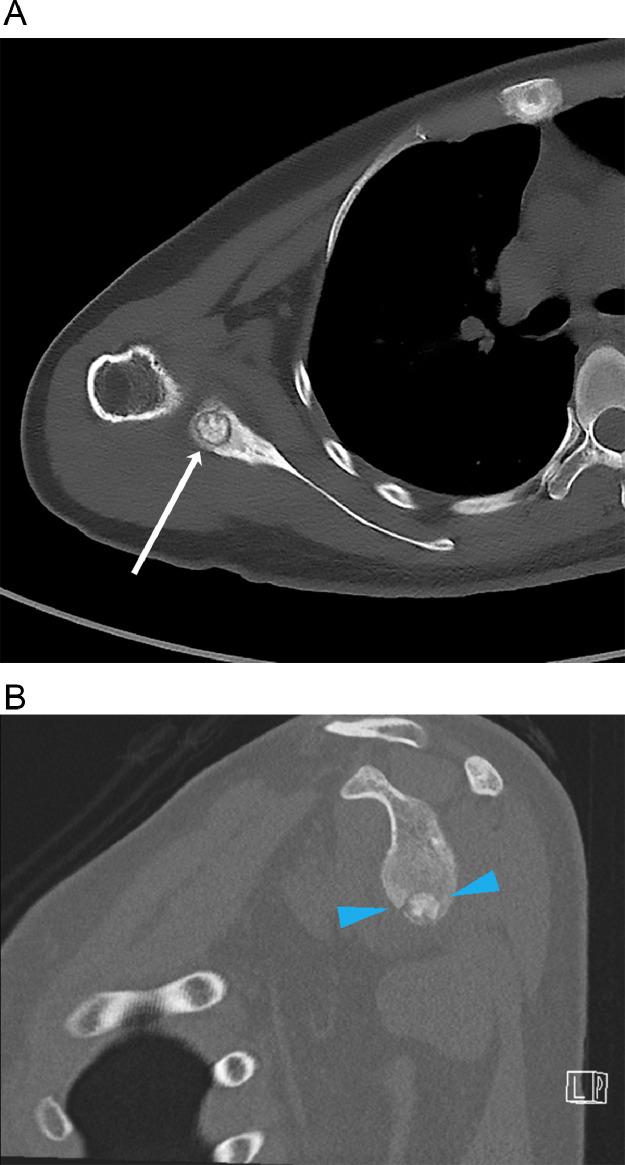

We report a case of an osteoid osteoma at the scapular glenoid that was treated with cryoablation. The patient presented with shoulder pain with subsequent CT and MRI imaging findings suspicious for an osteoid osteoma. The patient complained of persistent pain despite medical treatment and was referred to interventional radiology for consideration of ablation. CT-guided biopsy confirmed the diagnosis of osteoid osteoma and the patient underwent cryoablation of the lesion in the same session. The patient reported a substantial relief in her pain at a follow-up 4 weeks after the procedure. MRI performed 8 weeks after the procedure also confirmed radiographic remission of the lesion.